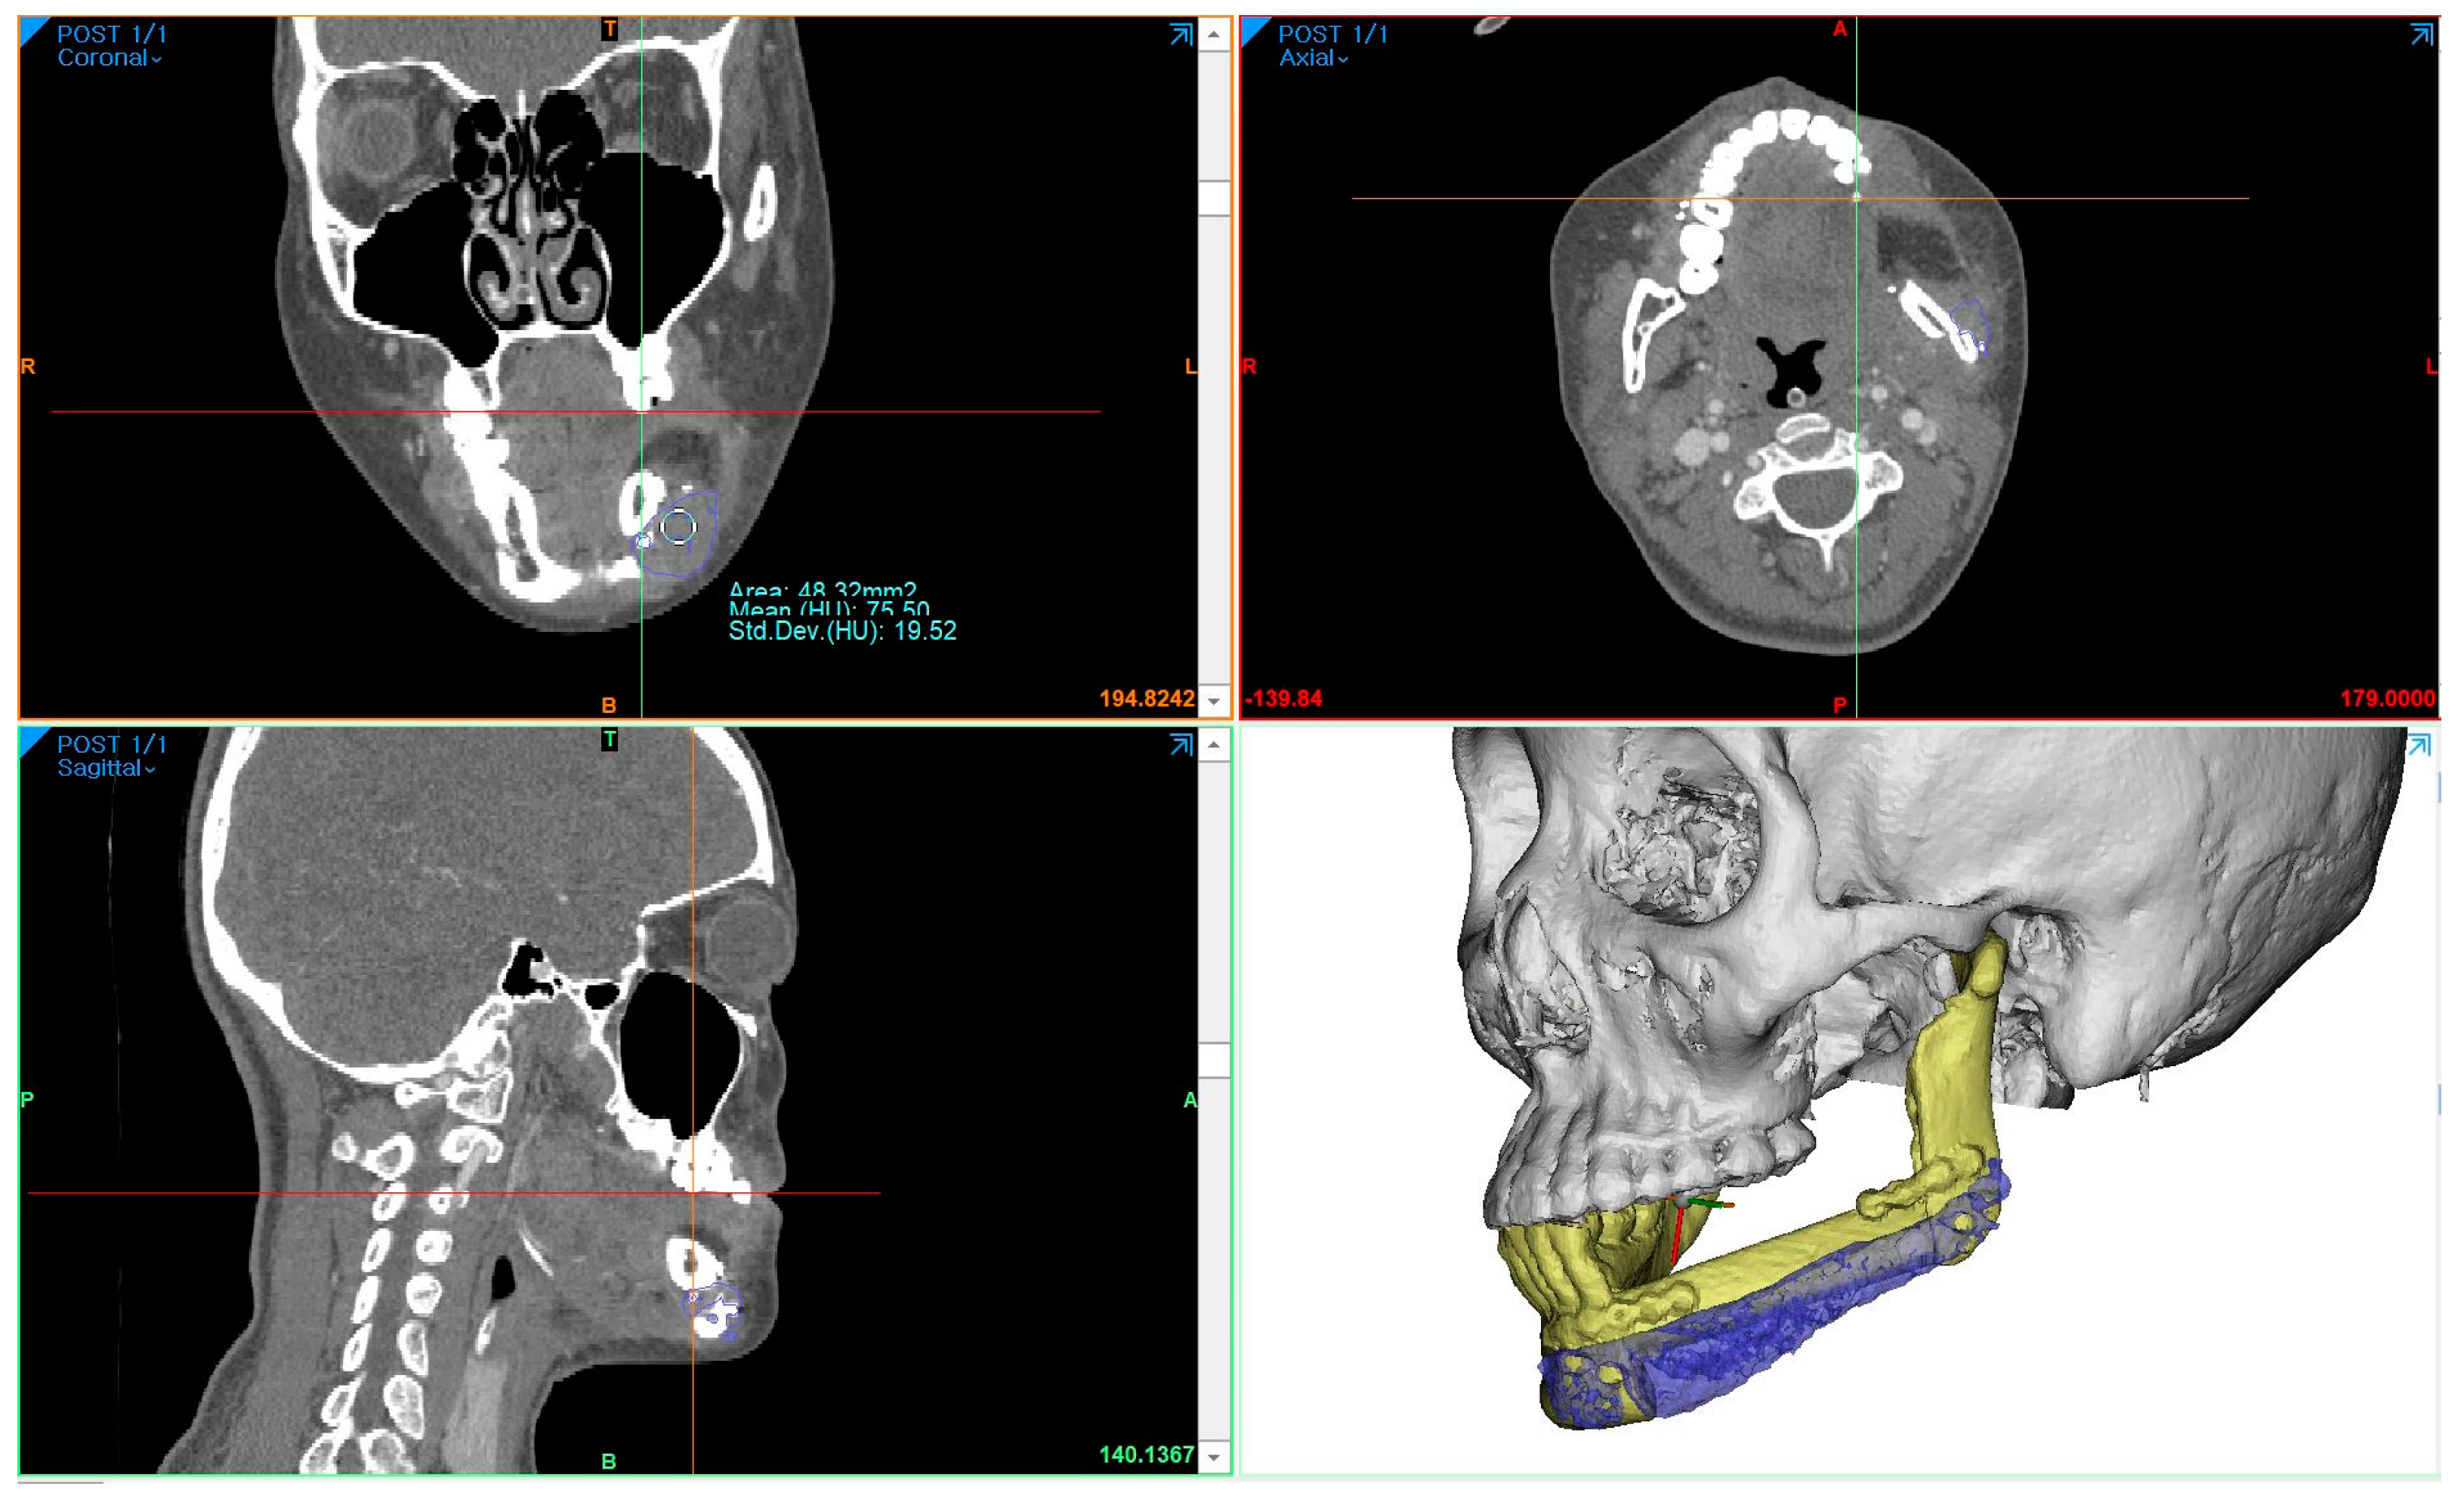

To measure the density of the PCL implant using follow-up-enhanced CT and Mimics software, the same location where the PCL was positioned at the level of the maxillary first molar was identified in the coronal view. At this specific location, the mean value and standard deviation of the Hounsfield units (HUs) were obtained using the “density” function (Figure 5). To compare accuracy on the same software, 3D models of surgical planning and the 3D model generated from the CT data taken two weeks after the operation were superimposed, and the error was calculated through mapping analysis.

The surgical results were analyzed using enhanced CT and MRI, which were radiographic images taken for the purpose of tracking malignant tumors. Follow-up CT scans were conducted at 2 weeks postoperatively and every year for the next 6 years, whereas MRI scans were performed only at 5 months, 11 months, 40 months, and 4-and-a-half years after surgery. The PCL implant exhibited similar attenuation to the surrounding soft tissue on the enhanced CT images, making it challenging to accurately generate a 3D model rendering in the Mimics software. The Hounsfield unit value of the PCL implant was measured using the “density” function in this software. It was observed that the density progressively increased over the years, from 75.50 at 2 weeks after surgery to 107.69 at 6 years after surgery (Figure 6). All average values were within the range of muscle thresholds. On the follow-up MRI, the PCL implant exhibited signals between the surrounding soft tissue and hard tissue, allowing for clear margin distinction. Consequently, changes in volume could be observed on the MRI, and there were no significant changes until 4-and-a-half years after surgery. The lattice pattern of the PCL, which was clearly observed until the 11-month postoperative MRI image, was absent in the 40-month postoperative MRI image, and it was analyzed that only the surface of the PCL had been replaced with soft tissue (Figure 7A,B). By superimposing the model immediately after surgery with the virtual plan, it was determined that the error was within 1 mm, except for the condylar head (Figure 7E).

Han et al. applied a patient-specific PCL scaffold to reconstruct a complex maxillary defect and reported stable and aesthetic surgical results [21]. The Hounsfield unit values of CT images at 6 months and 16 months after surgery were compared and analyzed as an increase in scaffold density. However, even on enhanced CT, the PCL part was distinguishable from the hard tissue but had a similar attenuation to the surrounding soft tissues. As a result, it was impossible to clearly demarcate the margin of the PCL, and only the extent of its position could be grasped. Therefore, in order to objectively compare the density of the PCL, HUs measured at the same location were required. In our case, the maxillary tooth and surrounding hemoclip in a fixed position were used as references. The HU values were acquired using the “density” function of the Mimics software. These values increased gradually each year, with all falling within the range of HU values for muscle. This observation suggested that the biodegradable PCL was replaced by soft tissues with a density similar to that of muscle, leading to an overall increase in density. Jeong et al. reported accurate and esthetic surgical outcomes of eight patients in zygomatico-maxillary reconstruction using a PCL/beta tricalcium phosphate (β-TCP) scaffold [22]. In their analysis of the results based on CT, a volume-rendering 3D model was created for the postsurgical implant to calculate the volume increase, and the HU values were measured to report the rate of new bone formation. However, due to the similar attenuation of the PCL implant to the nearby soft tissue, it was not possible to generate a volume-rendering model of the PCL implant alone in CT through segmentation. In contrast, on the MRI, the PCL implant showed intermediated signals between the hard tissue and the soft tissue; thus, it was possible to establish the boundary between the surrounding soft tissues. Even the PCL implant with interconnected lattice-type pores was observed as a lattice pattern on the MRI image. This grid pattern, which was clearly seen on MRI at 5 and 11 months after surgery, was not observed from MRI at 40 months postoperatively. Therefore, volume comparison of the PCL was possible with MRI, not CT. When comparing the latest follow-up MRI images taken 4-and-a-half years postoperatively, with previous MRI images, it was observed that the volume of the patient’s PCL implant itself did not change significantly. This finding was in contrast to reports of active disassembly occurring at 2 to 3 years in general conditions [19,20,26]. Additionally, it was seen that the surface of the PCL implant was replaced with soft tissue, having a signal similar to that of the muscle. Based on the fact that PCL is a biodegradable material, the above results could be interpreted as not regenerating into bone tissue at the resolved site but being replaced by the rigid soft tissue homogeneous to the muscle, so that the patient’s facial deformation may not occur.

Figure 5. Using the “density” function in Mimics software, the Hounsfield units’ value of the PCL implant area was obtained at the same location. In this case, the measurement of the same region was conducted at the level determined by the location of the hemoclip below the fibula segment and the maxillary first molar in the CT coronal view.